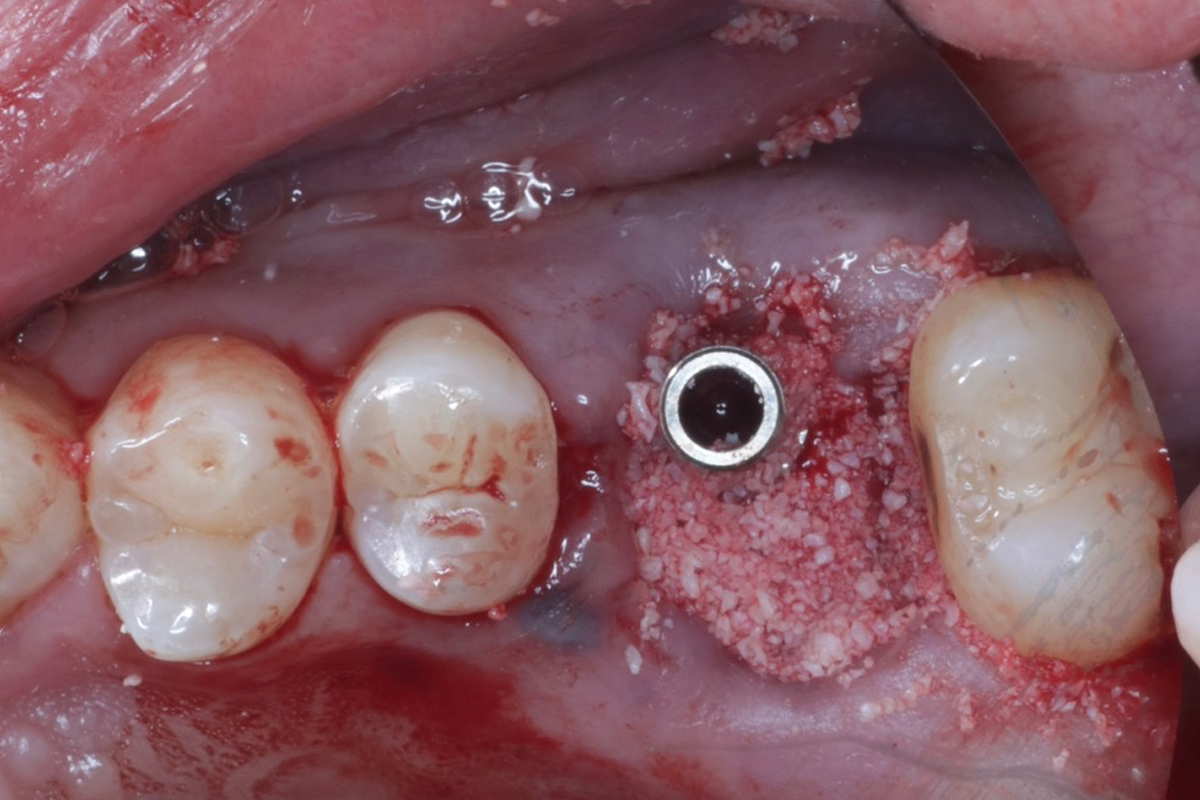

・臼歯部(奥歯)症例 [抜歯即時埋入]

①抜歯と同日にインプラント治療

抜歯即時埋入は術後に腫れ、内出血、痛みを伴うことが多い骨造成、歯肉移植を回避することができ、治療期間も短縮される治療方法です。通常、歯を抜いてから5〜6ヶ月待ってからインプラント治療を行いますが、抜歯即時埋入は5〜6ヶ月で治療は終わります。